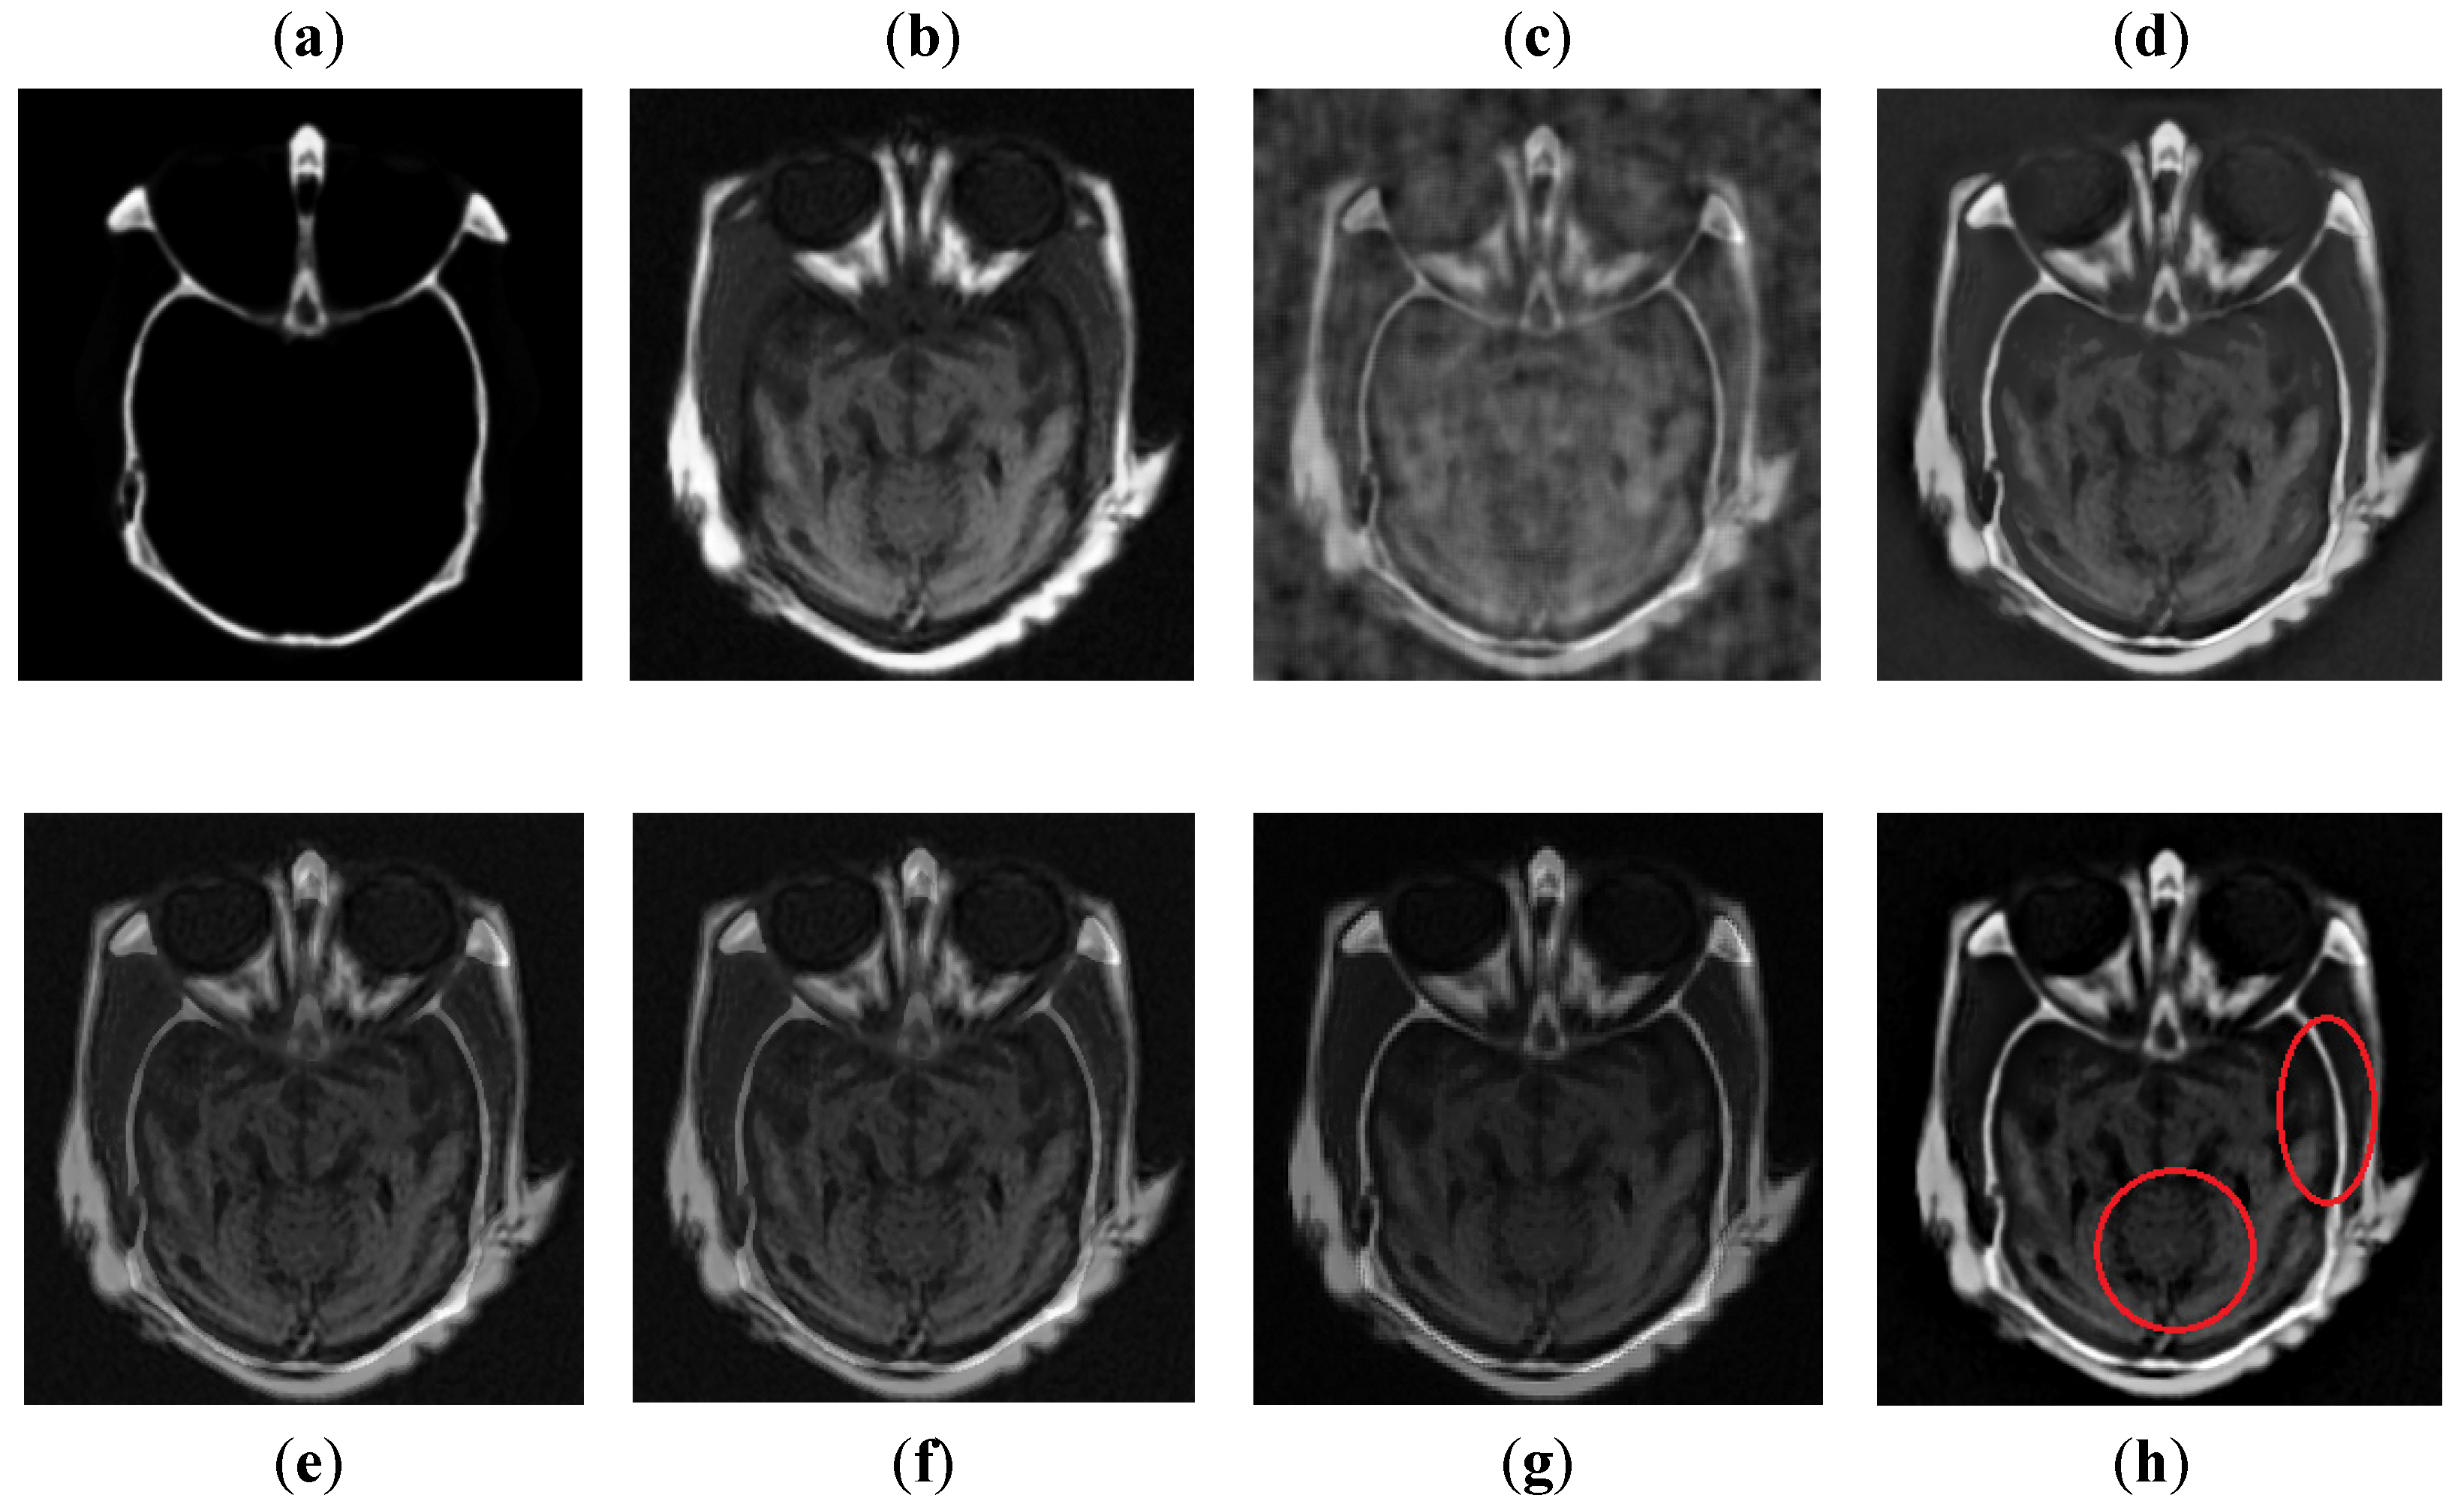

It can be visually observed in Figure 9 that the DCT method has more artifacts that distort the overall quality of a fused image. The DWT and NSST-SF-PCNN produce almost similar results, but DWT has more contrast and less noise than NSST-SF-PCNN. However, both methods have poor detailed and structured information that significantly loses valuable information about soft tissues. The CSR method effectively captures more information from the CT image, but due to non-uniform illumination, it drastically fails to restore more information about soft tissues from MRI image. On the other hand, the CNN method retains most of the information about soft tissues from an MRI image with good contrast, but it cannot completely capture edges and boundaries from a CT image that affect the image quality. The proposed method shows its superiority over other methods by producing a fused image that contains information from both source images. It has better contrast with very negligible artifacts. Additionally, it can be further explored from red boxes that the proposed method can effectively retain the soft tissues from MRI image and preserve bright and sharp detail about bones from a CT image.

Figure 9. Data-3: (a) CT image, (b) MRI image, (c) DCT, (d) DWT, (e) NSST-SFT-PCNN, (f) CSR, (g) CNN, and (h) Proposed.